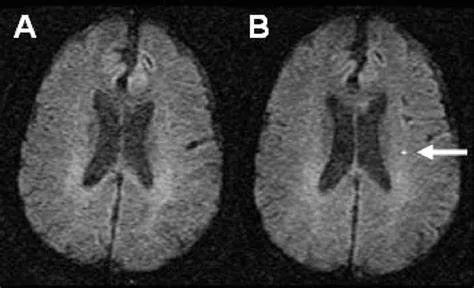

短暂性脑缺血发作通常会持续数分钟,随着症状持续时间的增加,梗死的可能性呈线性增加。MRI显示约40%出现短暂性脑缺血发作症状的患者出现病变,DWI阳性与1年后中风复发风险增加6倍以上有关。如果发现DWI阳性病变,通常会诊断为缺血性中风,然后入院治疗。DWI病变的分布有助于确定中风的发病机理(例如,深层结构中的单个腔隙提示小血管疾病;分散在多个区域的栓子可能指向心源性栓塞机制,如房颤[AF];病变的分水岭分布提示大血管疾病)并指导进一步的检查和二级预防策略。